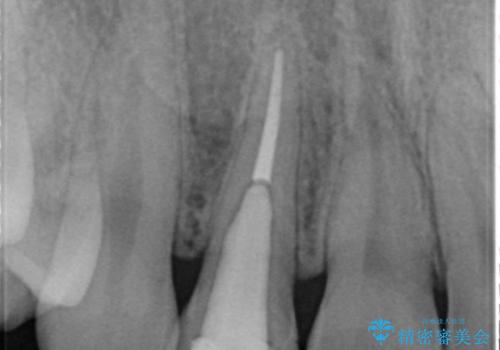

高校生の時に部活で前歯をぶつけて神経が死んでしまい、歯が黒く変色したためセラミッククラウンで治療したとのことでした。

精査したところ、透過性のあるセラミッククラウンで治療されており、内側の黒い土台が透けてクラウンが黒ずんで見えていました。

土台を白いファイバーコアにやりかえたのち、土台の色を透過させないジルコニアフレームを用いたセラミッククラウンによる治療を行いました。

失活(神経が死んでしまっていること)により黒くなった歯根が透けて歯ぐきも黒ずんで見えるため、歯肉移植の手術も提案しましたが、そこまでは気にならないとご希望されませんでした。